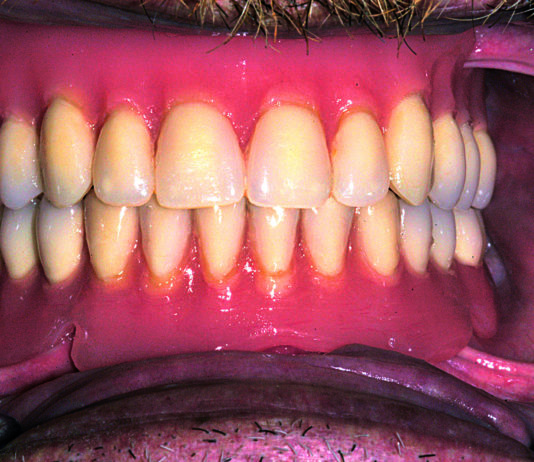

Trattamento estetico mucogengivale e rimodellamento della linea armonica del sorriso

Odontoiatra: Dr. Nicola Di Mare libero professionista in Modena

Trattamento: faccetta singola in disilicato di litio...